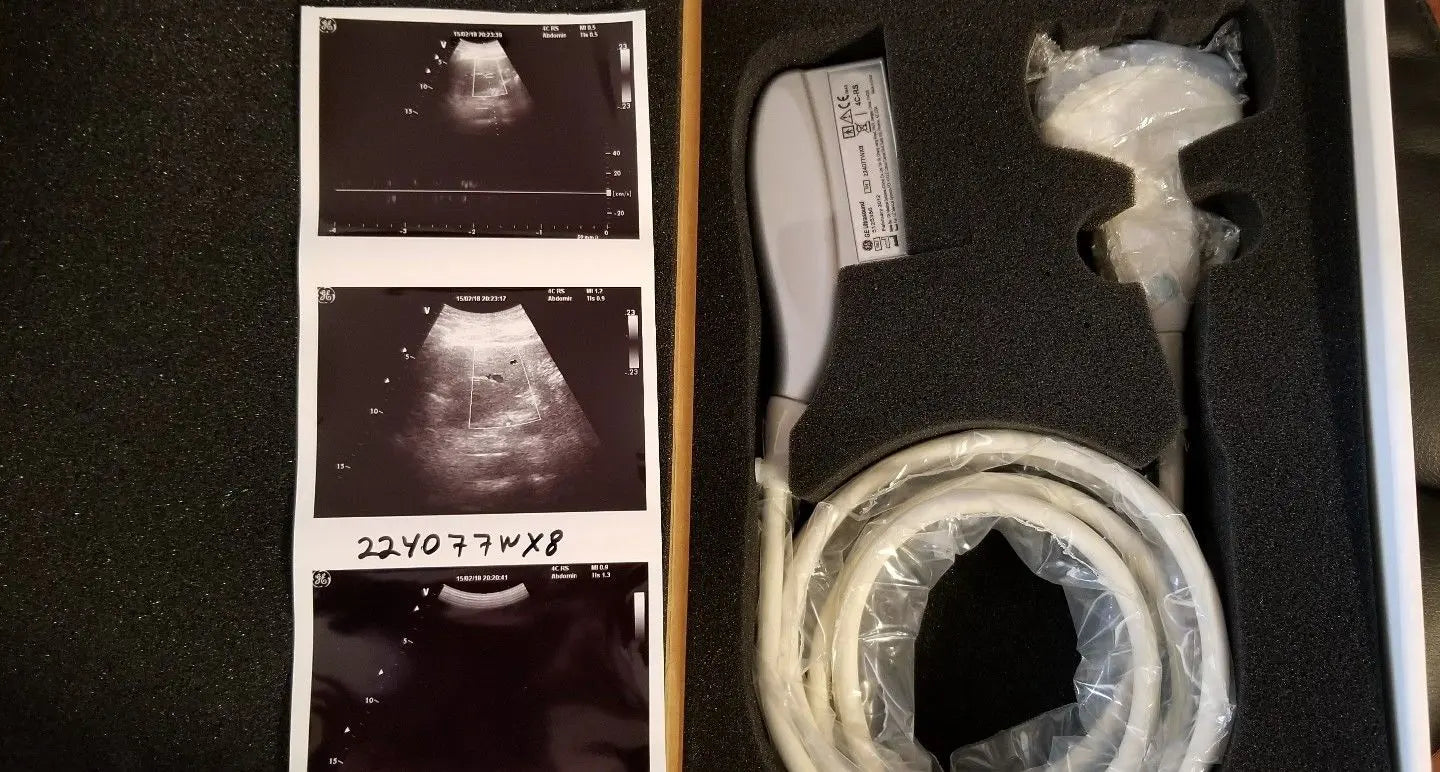

Description

Condition: Used: An item that has been used previously. The item may have some signs of cosmetic wear, but is fully operational and functions as intended. This item may be a floor model or store return that has been used. See the sellerâs listing for full details and description of any imperfections. See all condition definitions- opens in a new window or tab ... Read moreabout the condition

Brand: GE

Model: 4C-RS